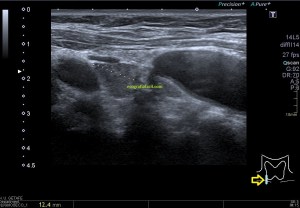

En la imagen 3 ves una imagen de un lipoma, mide 7 cms, la huella de la sonda mide 5cms, la «panoramic view» posee una regla centimetrada que sigue el contorno de la imagen, justo en la profundidad de la misma y lo marca la flecha amarilla. La profundidad la marca la flecha roja y la flecha blanca marca el rango centimetral de los 5cms, fíjate que la línea blanca es ligeramente mayor cada 5 cms. Sirve de referencia, como en la imagen 4 donde ves una colección en el glúteo de más de 10 cms.